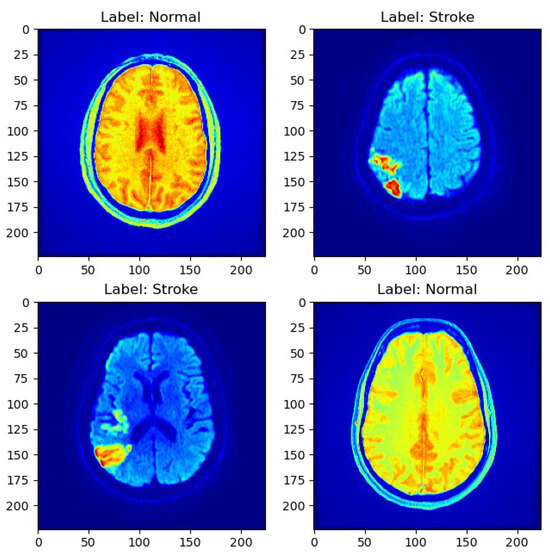

As depicted in Figure 1, a sample MRI scan exemplifies the diversity of cases present in the dataset, encompassing both normal and stroke cases.

Figure 1.

Sample MRI scans.